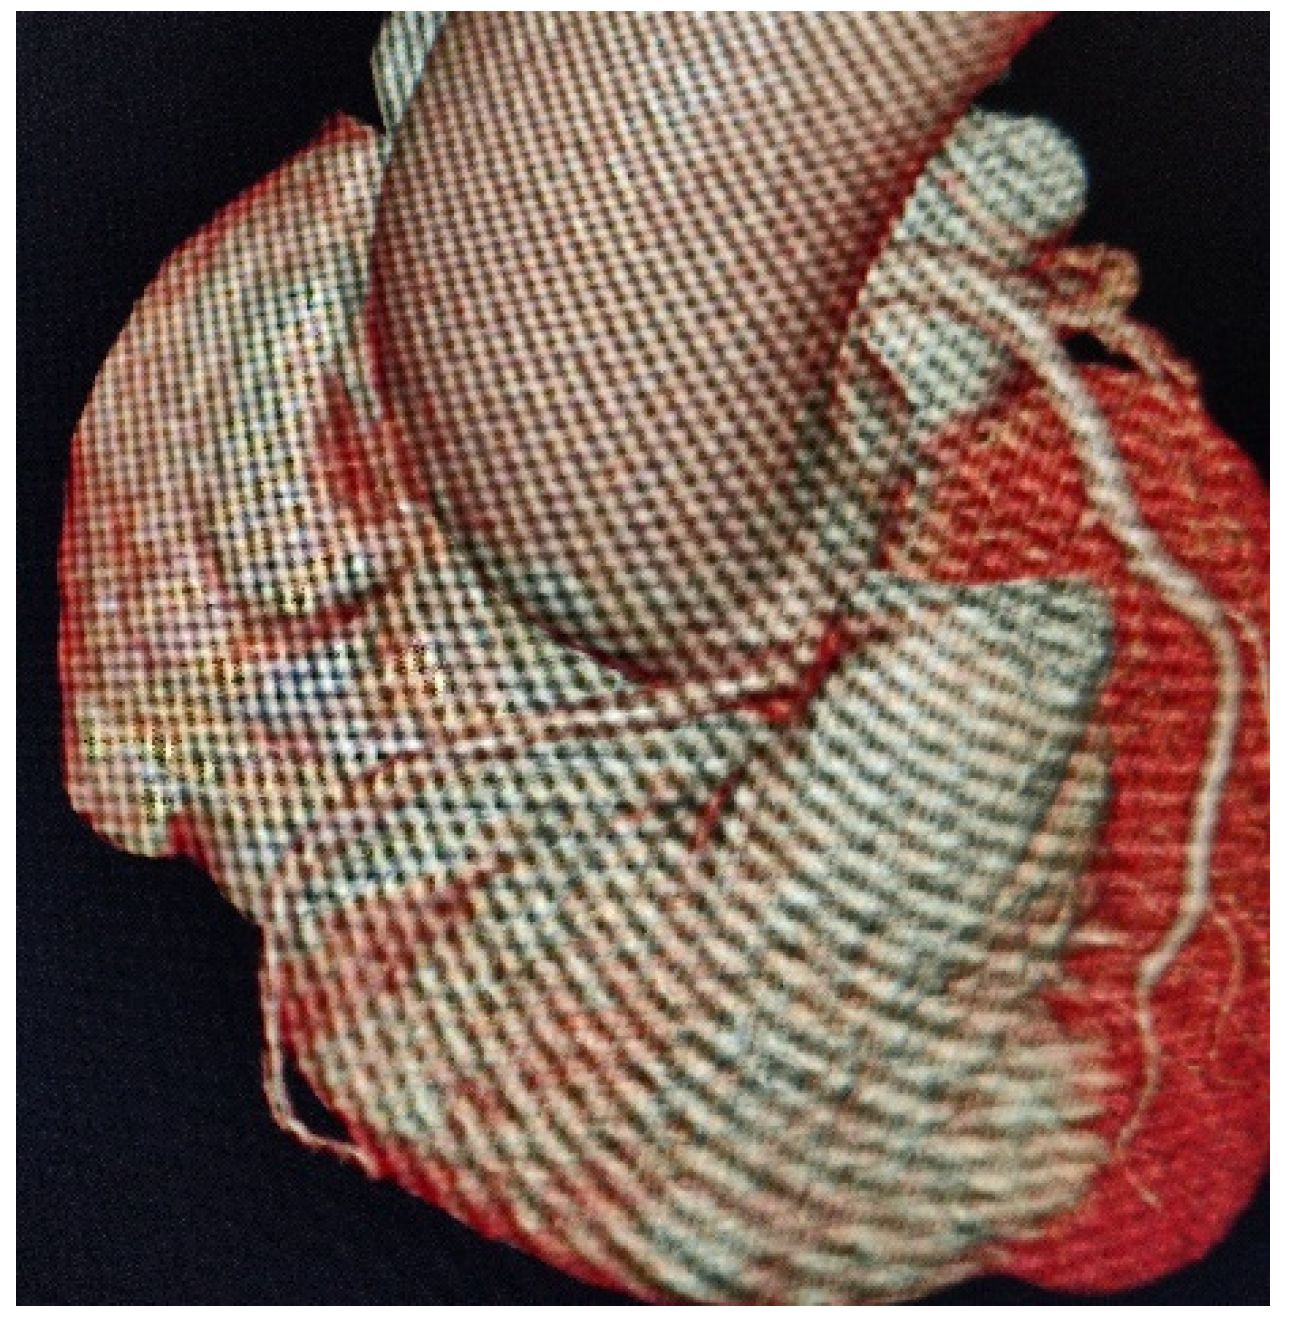

A Curve Maybe to Narrow: Description of an Anomalous Course of the Right Coronary Artery

Pastorini, G.; Bertone, E.; Talenti, A.; Feola, M. A Curve Maybe to Narrow: Description of an Anomalous Course of the Right Coronary Artery. Diseases 2021, 9, 62. https://doi.org/10.3390/diseases9030062